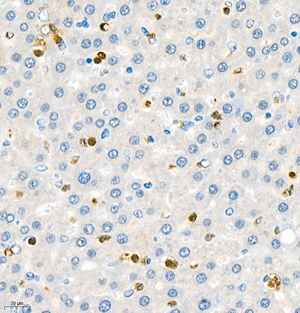

| IHC analysis of mpo (GB11224). Sample: Human liver (Paraffin), 4% PFA (G1101) 12-24h. Antigen retrieval: Citrate buffer (pH 6.0) (G1201),98°C,20 min. Blocking buffer: 3% BSA in PBS (GC305010), RT, 30min. Primary antibody: 1: 1000, 4°C overnight. Secondary antibody: HRP Goat Anti-Rabbit lgG (GB23303), 1: 200 RT 1h. |